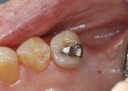

Joe Cha #20 prep